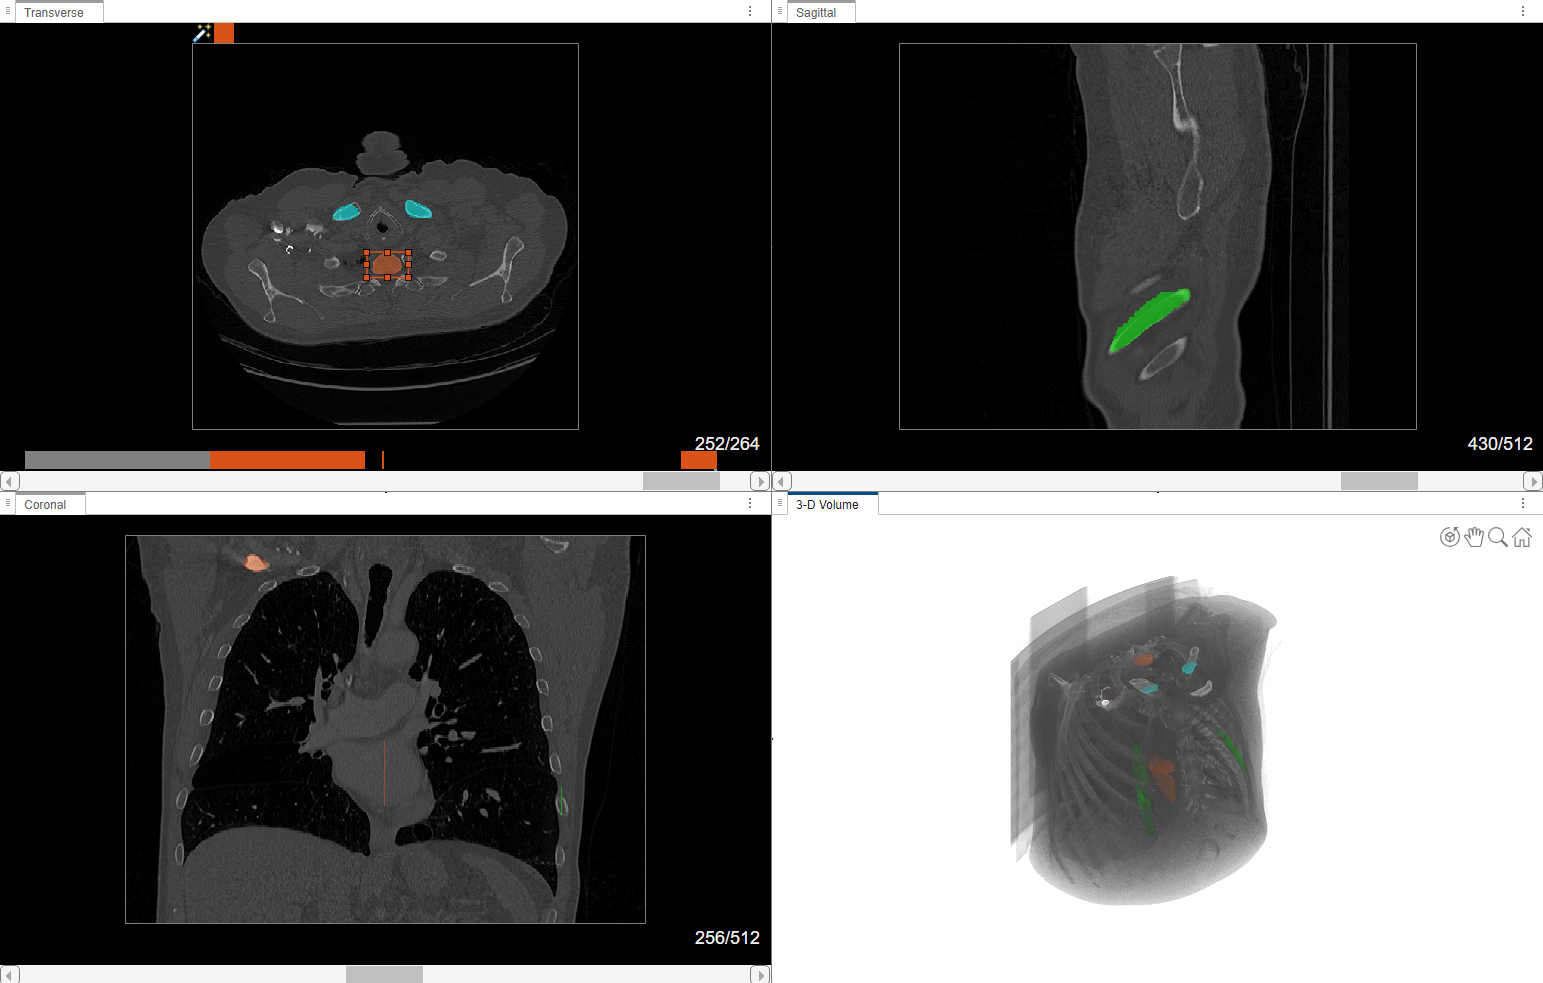

Visually Explore Data

The app displays 3-D image data using individual panes for the Transverse, Sagittal, and Coronal slice planes and a 3-D Volume pane. For an example of how to customize the display of 3-D images, and publish images and animations, see Visualize 3-D Medical Image Data Using Medical Image Labeler. The app displays 2-D image data in the Slice pane. For details about navigating frames or adjusting the brightness and contrast of a 2-D image series, see Label 2-D Ultrasound Series Using Medical Image Labeler.

These images show CT scans labeled using automated MONAI Label models in the Medical Image Labeler app.